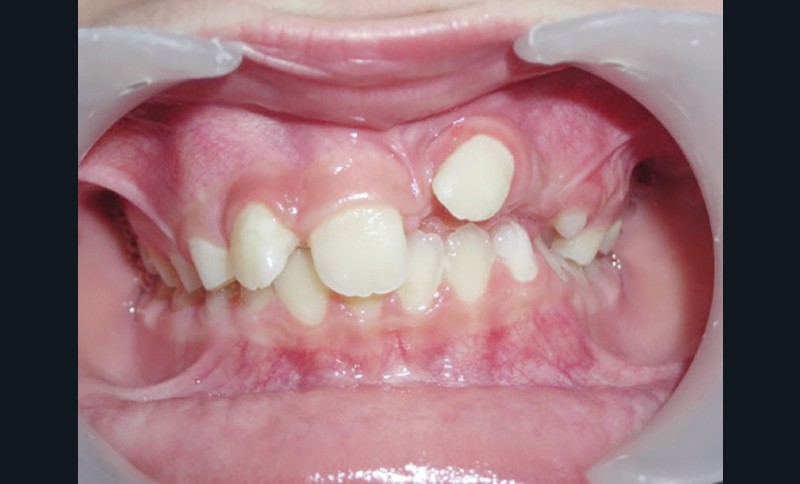

Le jeune Yoan 9 ans est adressé par son chirurgien maxillofacial, suite à l’exérèse d’un kyste bénin du maxillaire, et l’avulsion de 21 et 23 (fig. 1). L’apex de 22 a été soufflé par le kyste. La céphalométrie (fig. 2a et b) et l’examen clinique mettent en évidence une classe II squelettique par rétromandibulie, ainsi qu’une classe II dentaire. Le patient, est particulièrement perturbé par l’intervention qu’il vient de subir, et la coopération s’annonce difficile.

La gestion esthétique immédiate passe par un traitement orthodontique précoce, car la position de 22 (fig. 3) empêche toute restauration provisoire de l’édentement. Au vu du contexte, le choix thérapeutique se portera sur la simplicité, la rapidité, l’esthétique puis la réévaluation sur le long terme.